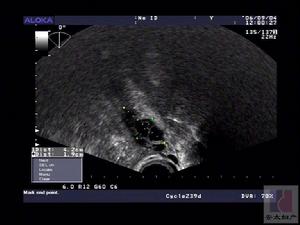

5、B超检查了解卵巢有无多囊性改变。 医学百科网 | YxBaike.Com